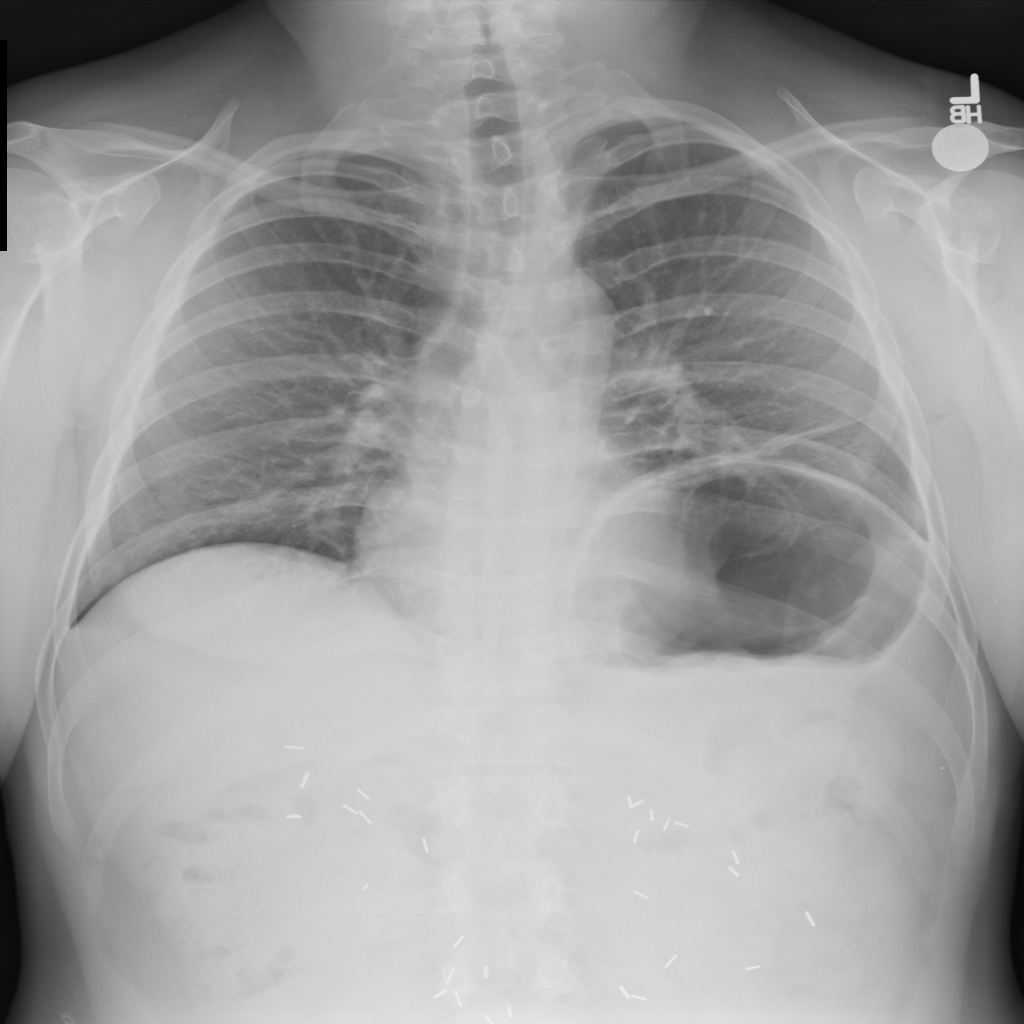

PAT-E960 · IMG-002Fibrosis

PAT-E960 · IMG-002

PA